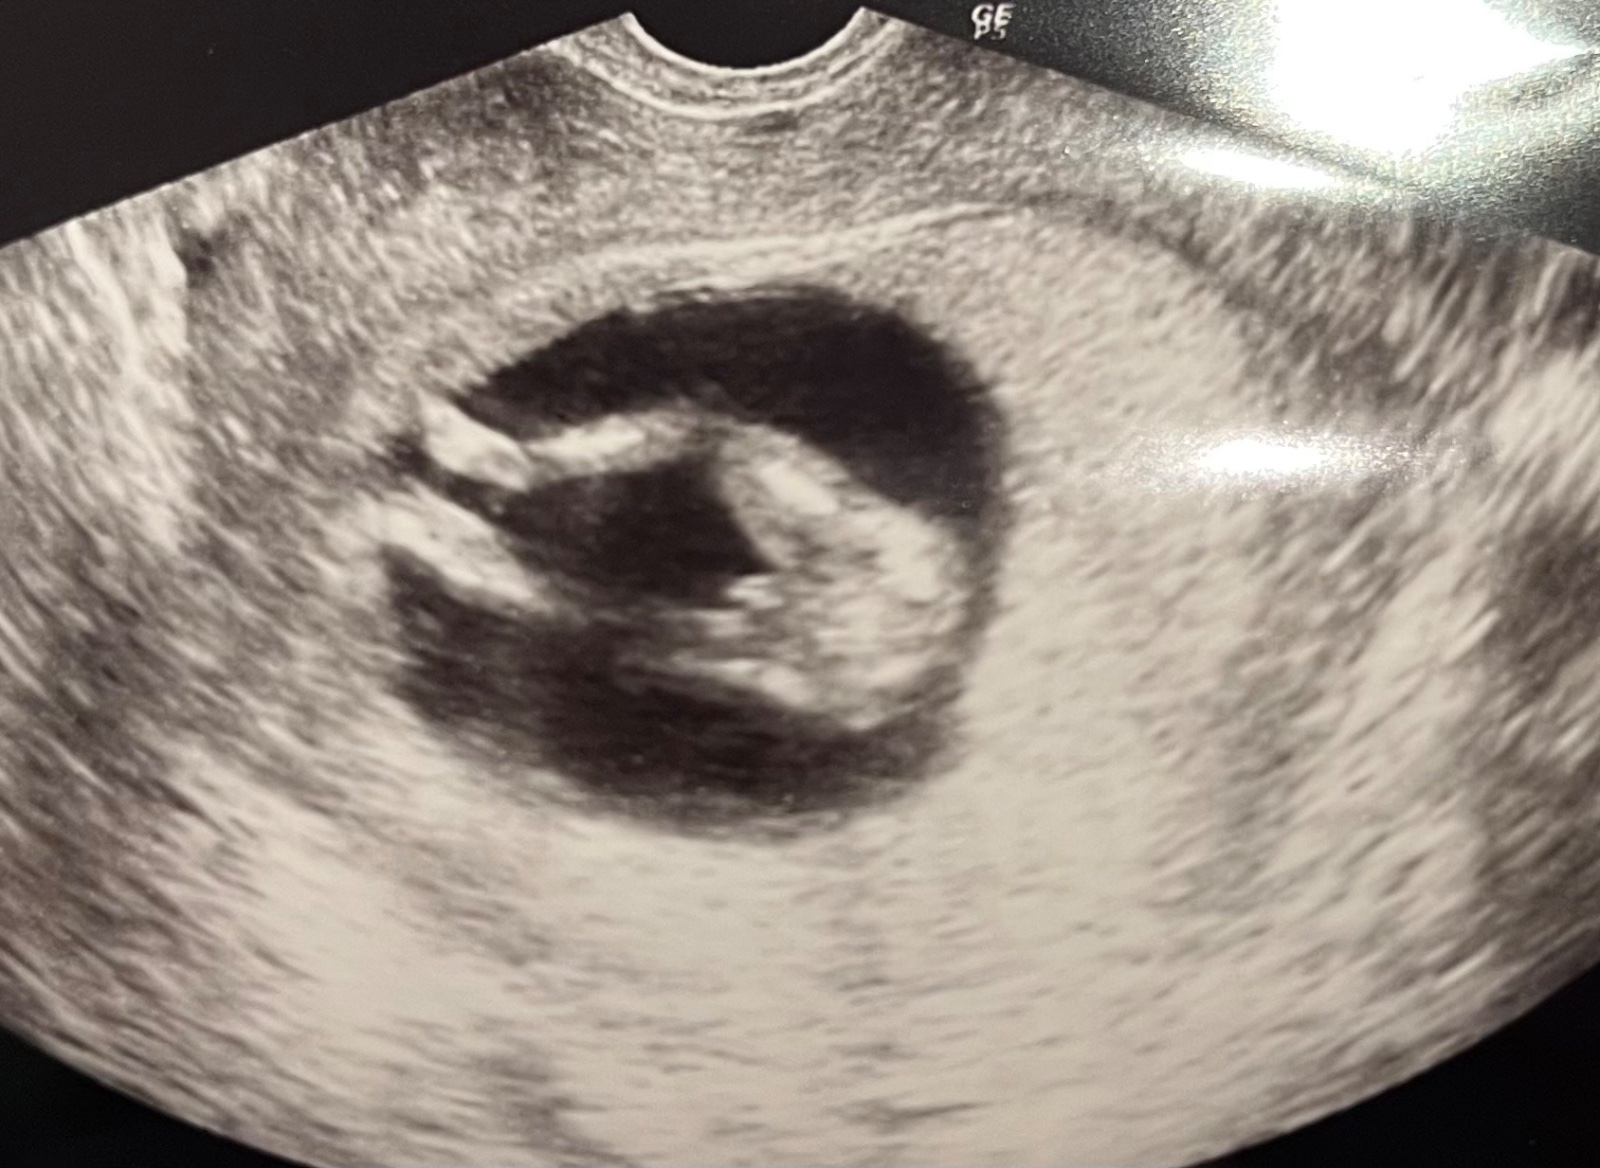

Aké pohlavie vidíte na ultrazvuku?

presne takúto fotku mam aj ja od prvého syna z pred 15tich rokov a bol to chlapec

Veľmi podobné som mala v 13tt aj ja. Lekár (špecialista na rizikové tehotenstvá) mi povedal, že je to na 1000% (slovom tisíc) chlapec. Už o 2 mesiace na pravidelnej kontrole bolo vidieť, že je to dievča a aj sa narodilo dievča.

vyzera to ako chlapec,a le moze tam pretrcat aj upocna snura, cize to moze byt hocijake pohlavie.

nic nie je iste. je dobre pozriet z viacerych stran a neskor. cim neskor, tym vacsia istota.